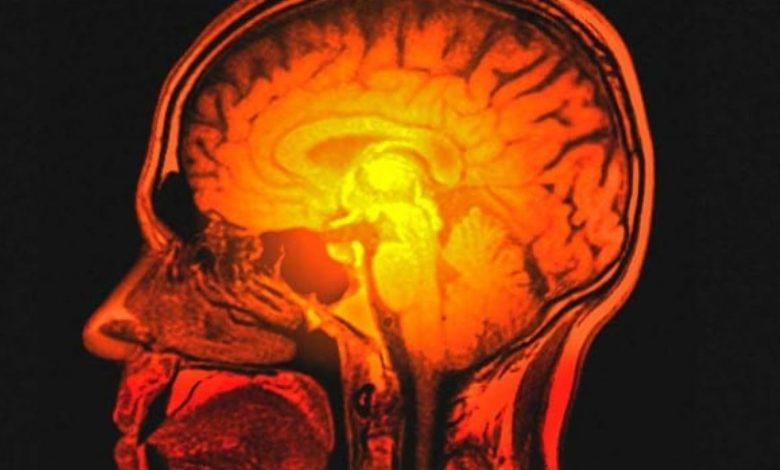

Beyin ve omuriliğin içerisindeki boşluklarda ve bu yapıları çevreleyen zarların arasında yer alan sıvıya “beyin omurilik sıvısı (BOS) ismi verilmektedir. Normal şartlarda içerisinde mikroorganizma içermeyen berrak bir sıvı olan BOS’un farklı katmanlardan oluşan beyin zarının içinde kalması ve dış ortamla irtibatının olmaması gerekir. Beyin ve omuriliği çevreleyen zar yapısının en güçlü ve koruyucu katmanı en dışta bulunan ve Dura olarak isimlendirilen tabakasıdır. Çeşitli sebeplerle Dura’da hasar oluşmasına bağlı olarak BOS’un dış ortama sızması BOS kaçağı veya BOS fistülü, bu sızıntının burun ve etrafındaki sinüs boşluklarına doğru olması sonucunda burundan berrak bir akıntı gelmesi ise “Rinore” olarak isimlendirilmektedir.

Sinüs ameliyatı olan hastalarda ameliyat bölgesinin endoskopik olarak değerlendirilmesi teşhise yardımcı olmakla birlikte kesin teşhis burundan akan berrak sıvının laboratuvar analizi ile konulabilmektedir. Teşhis kesinleştikten sonra tedavinin planlanabilmesi için kaçak bölgesinin tespit edilmesi gerekir. Bu amaçla bilgisayarlı tomografi ve MR başta olmak üzere değişik radyolojik değerlendirmeler yapılmakta, kaçak bölgesinin standart görüntüleme teknikleri ile belirlenemediği durumlarda bu tespitin BOS içine özel boyalar verilerek burun içinden endoskopik muayene ile yapılması gerekebilmektedir.